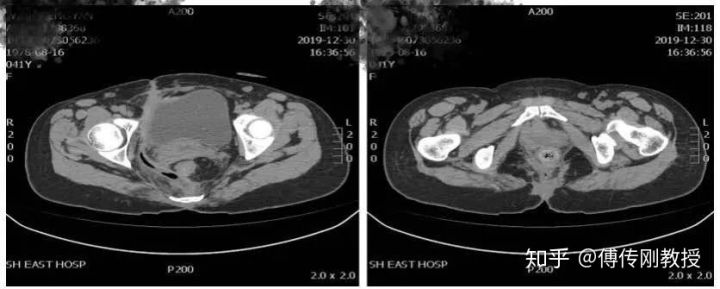

入院腹部CT

2020.01.14医生给我腰麻下行骶尾部窦道切开、脓肿引流术。手术记录显示术中探查齿状线上3cm可触及直肠后壁瘘口约0.5cm,内有少量陈旧性干结大便。囊腔位于直肠右后间隙,约12*10*5cm,内有脓液和少量坏死组织。

腹部CT